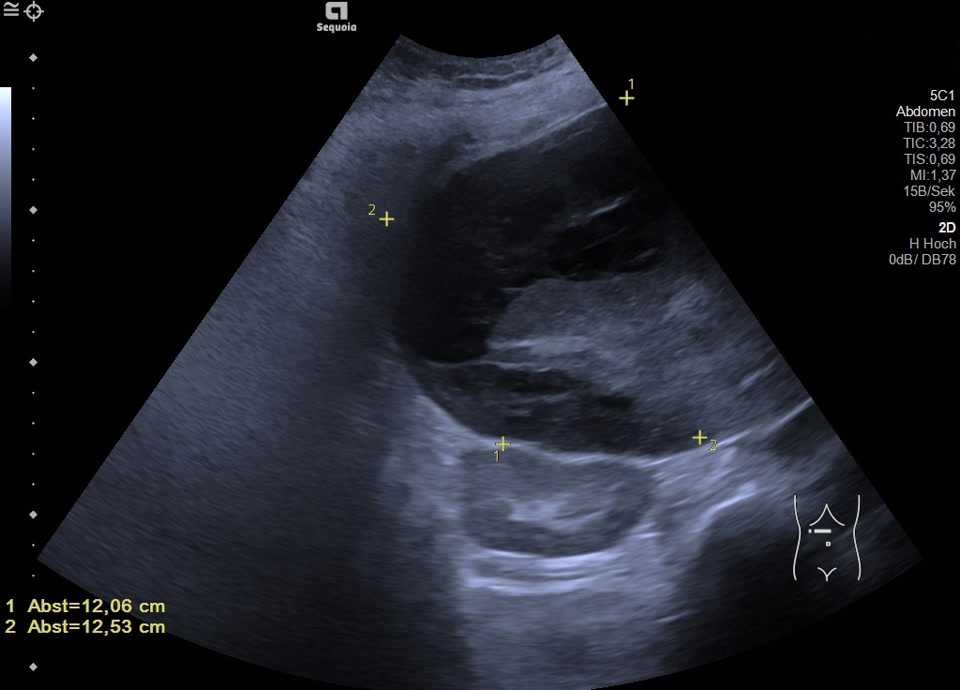

Leberhämatom (HELLP-Syndrom)

Kasuistik: die 48-jährige Patientin hat während ihrer Schwangerschaft ein HELLP-Syndrom entwickelt. Zustand nach Sectio bei schwerer Präeklampsie und Gemini in der 37. SSW. Post-partales HELLP mit Leberhämatom und beginnendem Leber- und Nierenversagen. Durch die Interventionelle Radiologie erfolgte die CT-gestütze Embolisation mit Coils. Sonographisch stellt sich jetzt ein 12x13cm messendes subkapsuläres Hämatom im rechten Leperlappen mit Anzeichen einer beginnenden Organisation dar. Die Läsion nimmt kein Kontrastmittel auf, eine aktive Blutung kann ausgeschlosen werden.